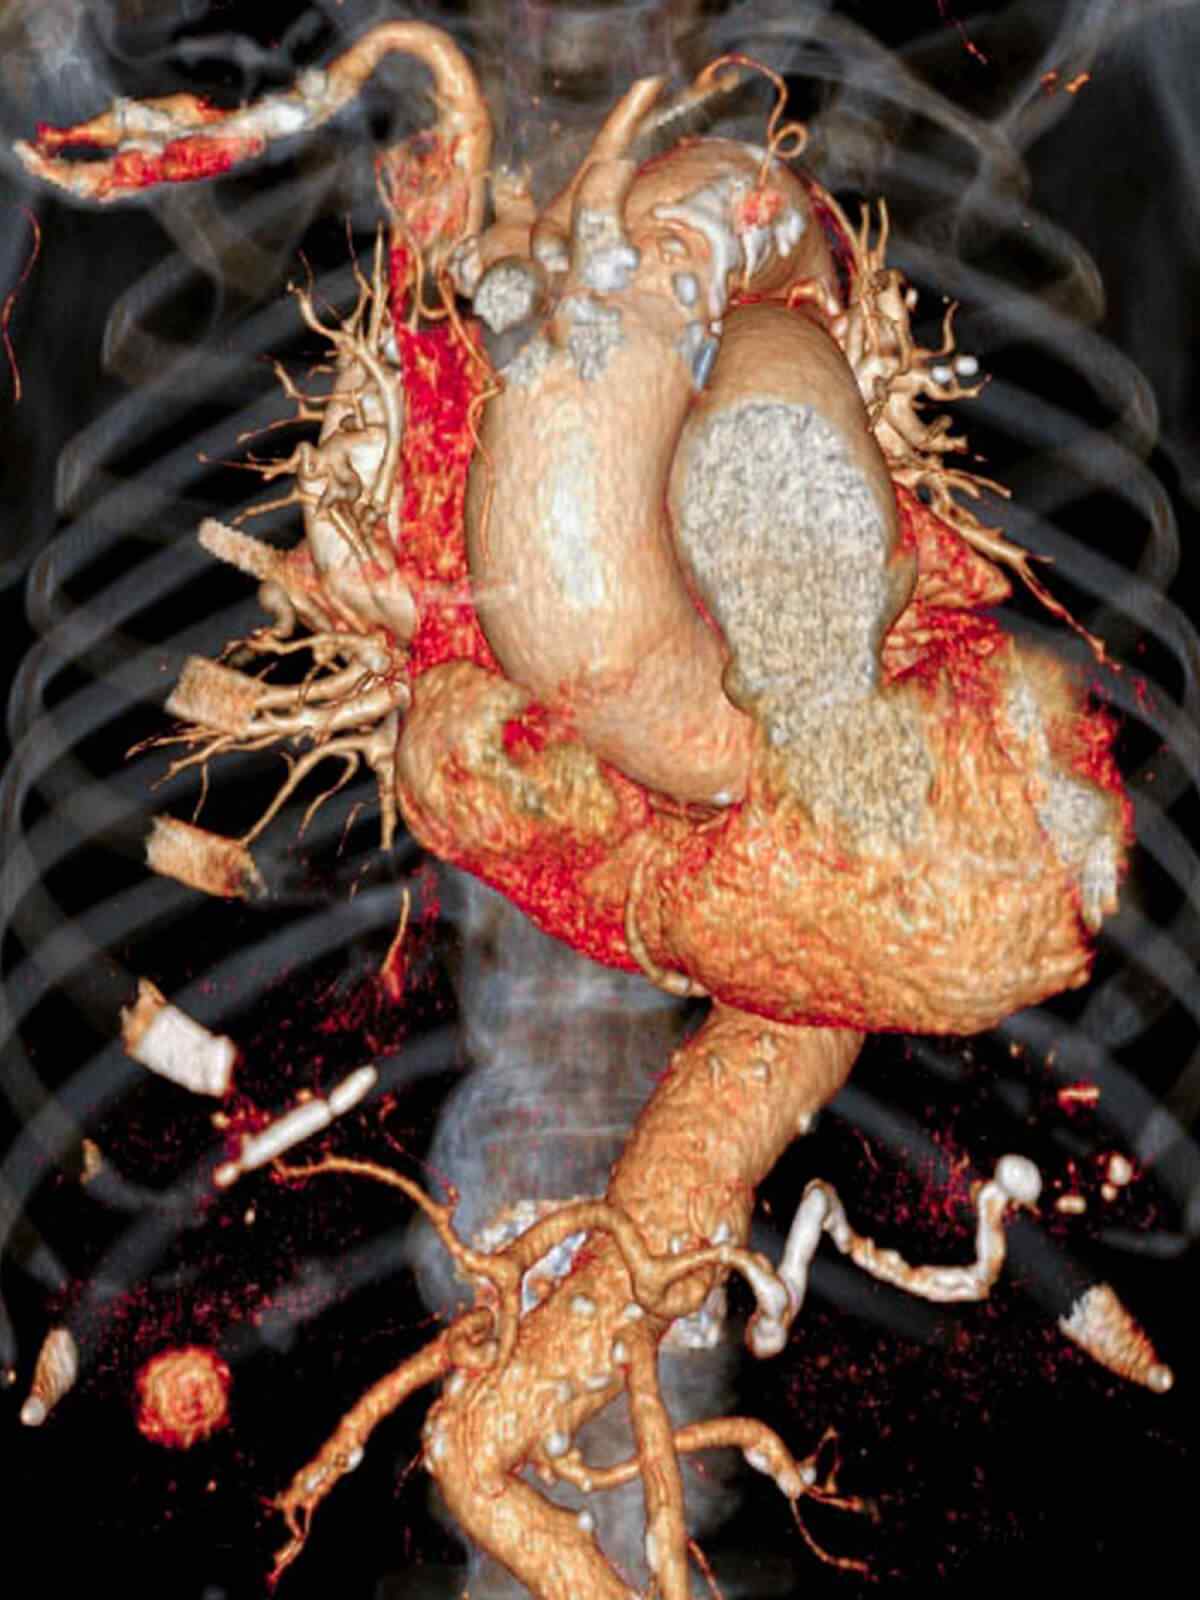

If you have known coronary artery disease, your doctor might recommend the traditional approach because you can also receive treatment during the procedure. Your doctor should give you instructions about how to prepare for CT.